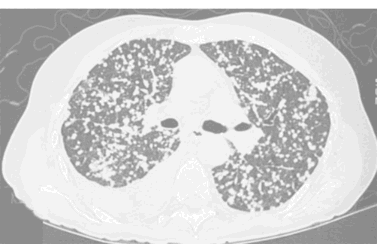

How would you describe the LUNG abnormality in each of these cases?

A